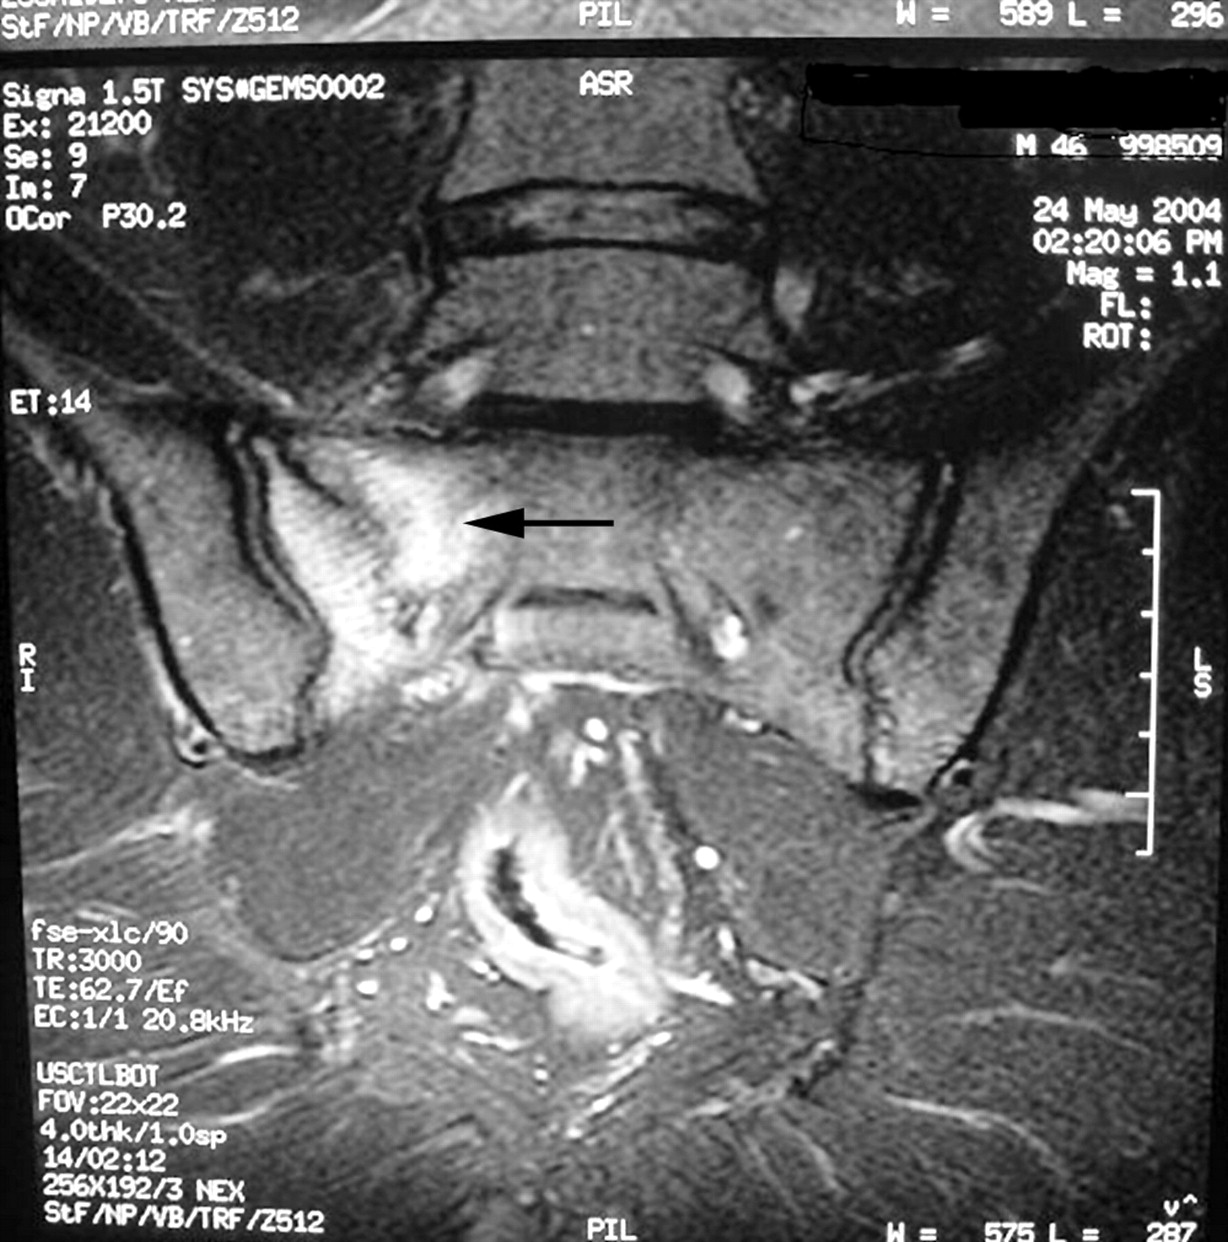

Sacral Stress Fractures